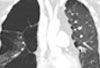

A 26-year-old man presented with sudden onset of palpitations and shortness of breath after incidentally taking tadalafil. He had no other symptoms and no history of illnesses during childhood. He drank socially but denied smoking and use of illicit drugs.